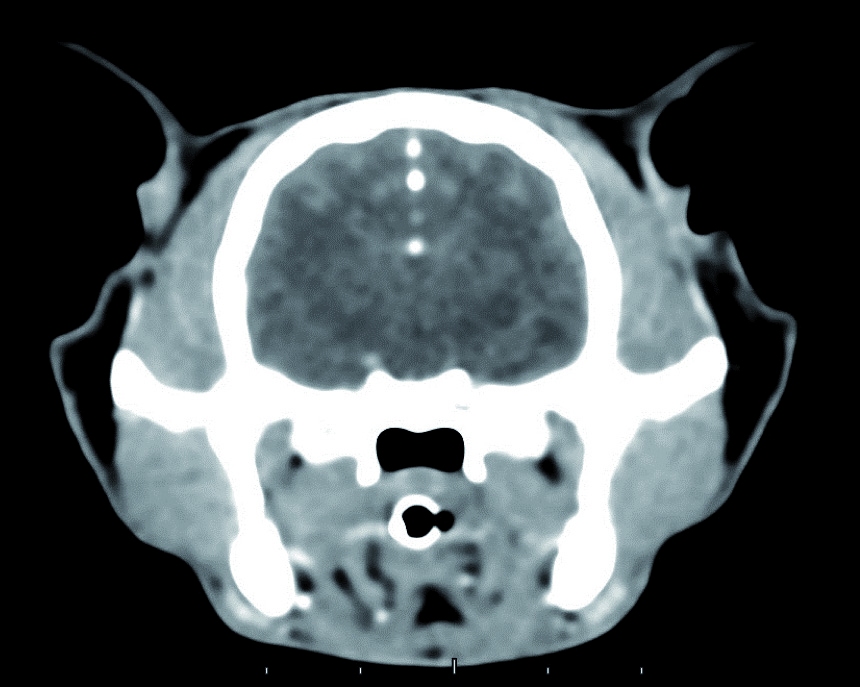

La tecnologia è stata sviluppata pensando agli esseri umani, ma la sua compattezza e il costo contenuto – abbinate a ottime funzionalità di base – l’hanno resa una soluzione particolarmente adatta anche alle necessità dell’ambito veterinario. Oltre a una migliorata risoluzione spaziale, la nuova tecnologia garantisce diagnosi più accurate e meno invasive grazie a software innovativi che consentono l’ottimizzazione della dose di radiazioni erogate, la visualizzazione in 3D delle immagini esaminate, l’analisi automatica dei vasi, l’endoscopia virtuale e la colonografia TC.

I vantaggi sono molteplici: un esame TC consente di valutare al meglio la presenza di eventuali metastasi, di studiare i margini di masse per preparare al meglio un eventuale intervento operatorio o, mediante l’utilizzo di mezzi di contrasto specifici, di diagnosticare problemi vascolari potenzialmente non esplorabili con altre metodiche di imaging.